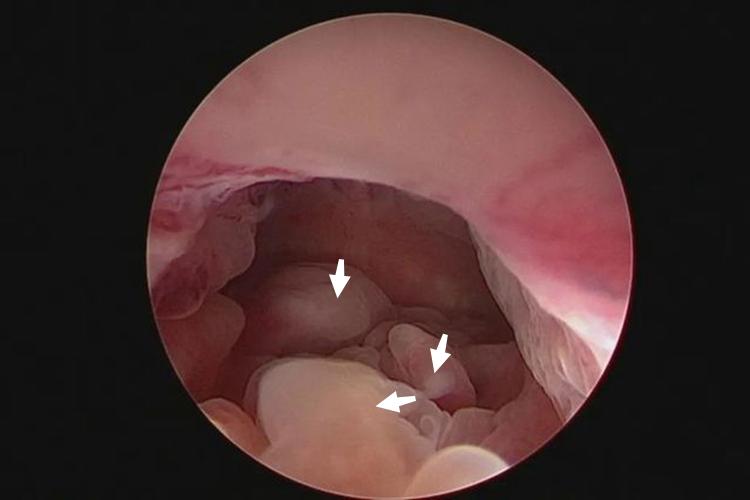

宫腔息肉一般指子宫内膜息肉,是子宫局部内膜过度生长所致。宫腔镜下可见宫腔内有单个或多个凸起物,直径从数毫米到数厘米,可分为无蒂和有蒂。同时患者常出现异常子宫出血,表现为月经过多、经间出血、不规则出血、不孕等症状。